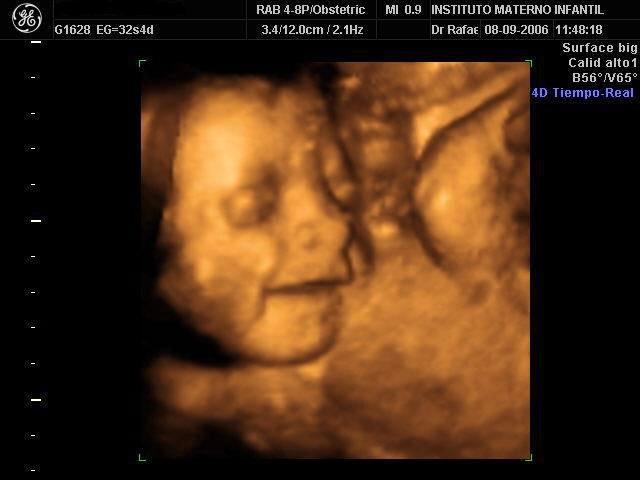

En China, el endémico feminicidio ya era descrito por el explorador Marco Polo, o por el filósofo Han Fei quien en el siglo III AEC escribía: "Un padre y madre cuando producen un niño se felicitan el uno al otro... Pero si producen una niña le dan muerte"... Hoy por hoy y debido a la política de "un sólo hijo", se afirma que podrían existir hasta 25 millones menos de chinas de las que cabría esperar de un criterio de selección natural... muchas de ellas perecerían ahogadas en el Yangtze, entre otros ríos y nada más nacer... El uso ilegal del ultrasonido está difundido en China, con sonógrafos itinerantes en camionetas aparcadas, ofreciendo ecografías baratas para determinar el sexo del feto.